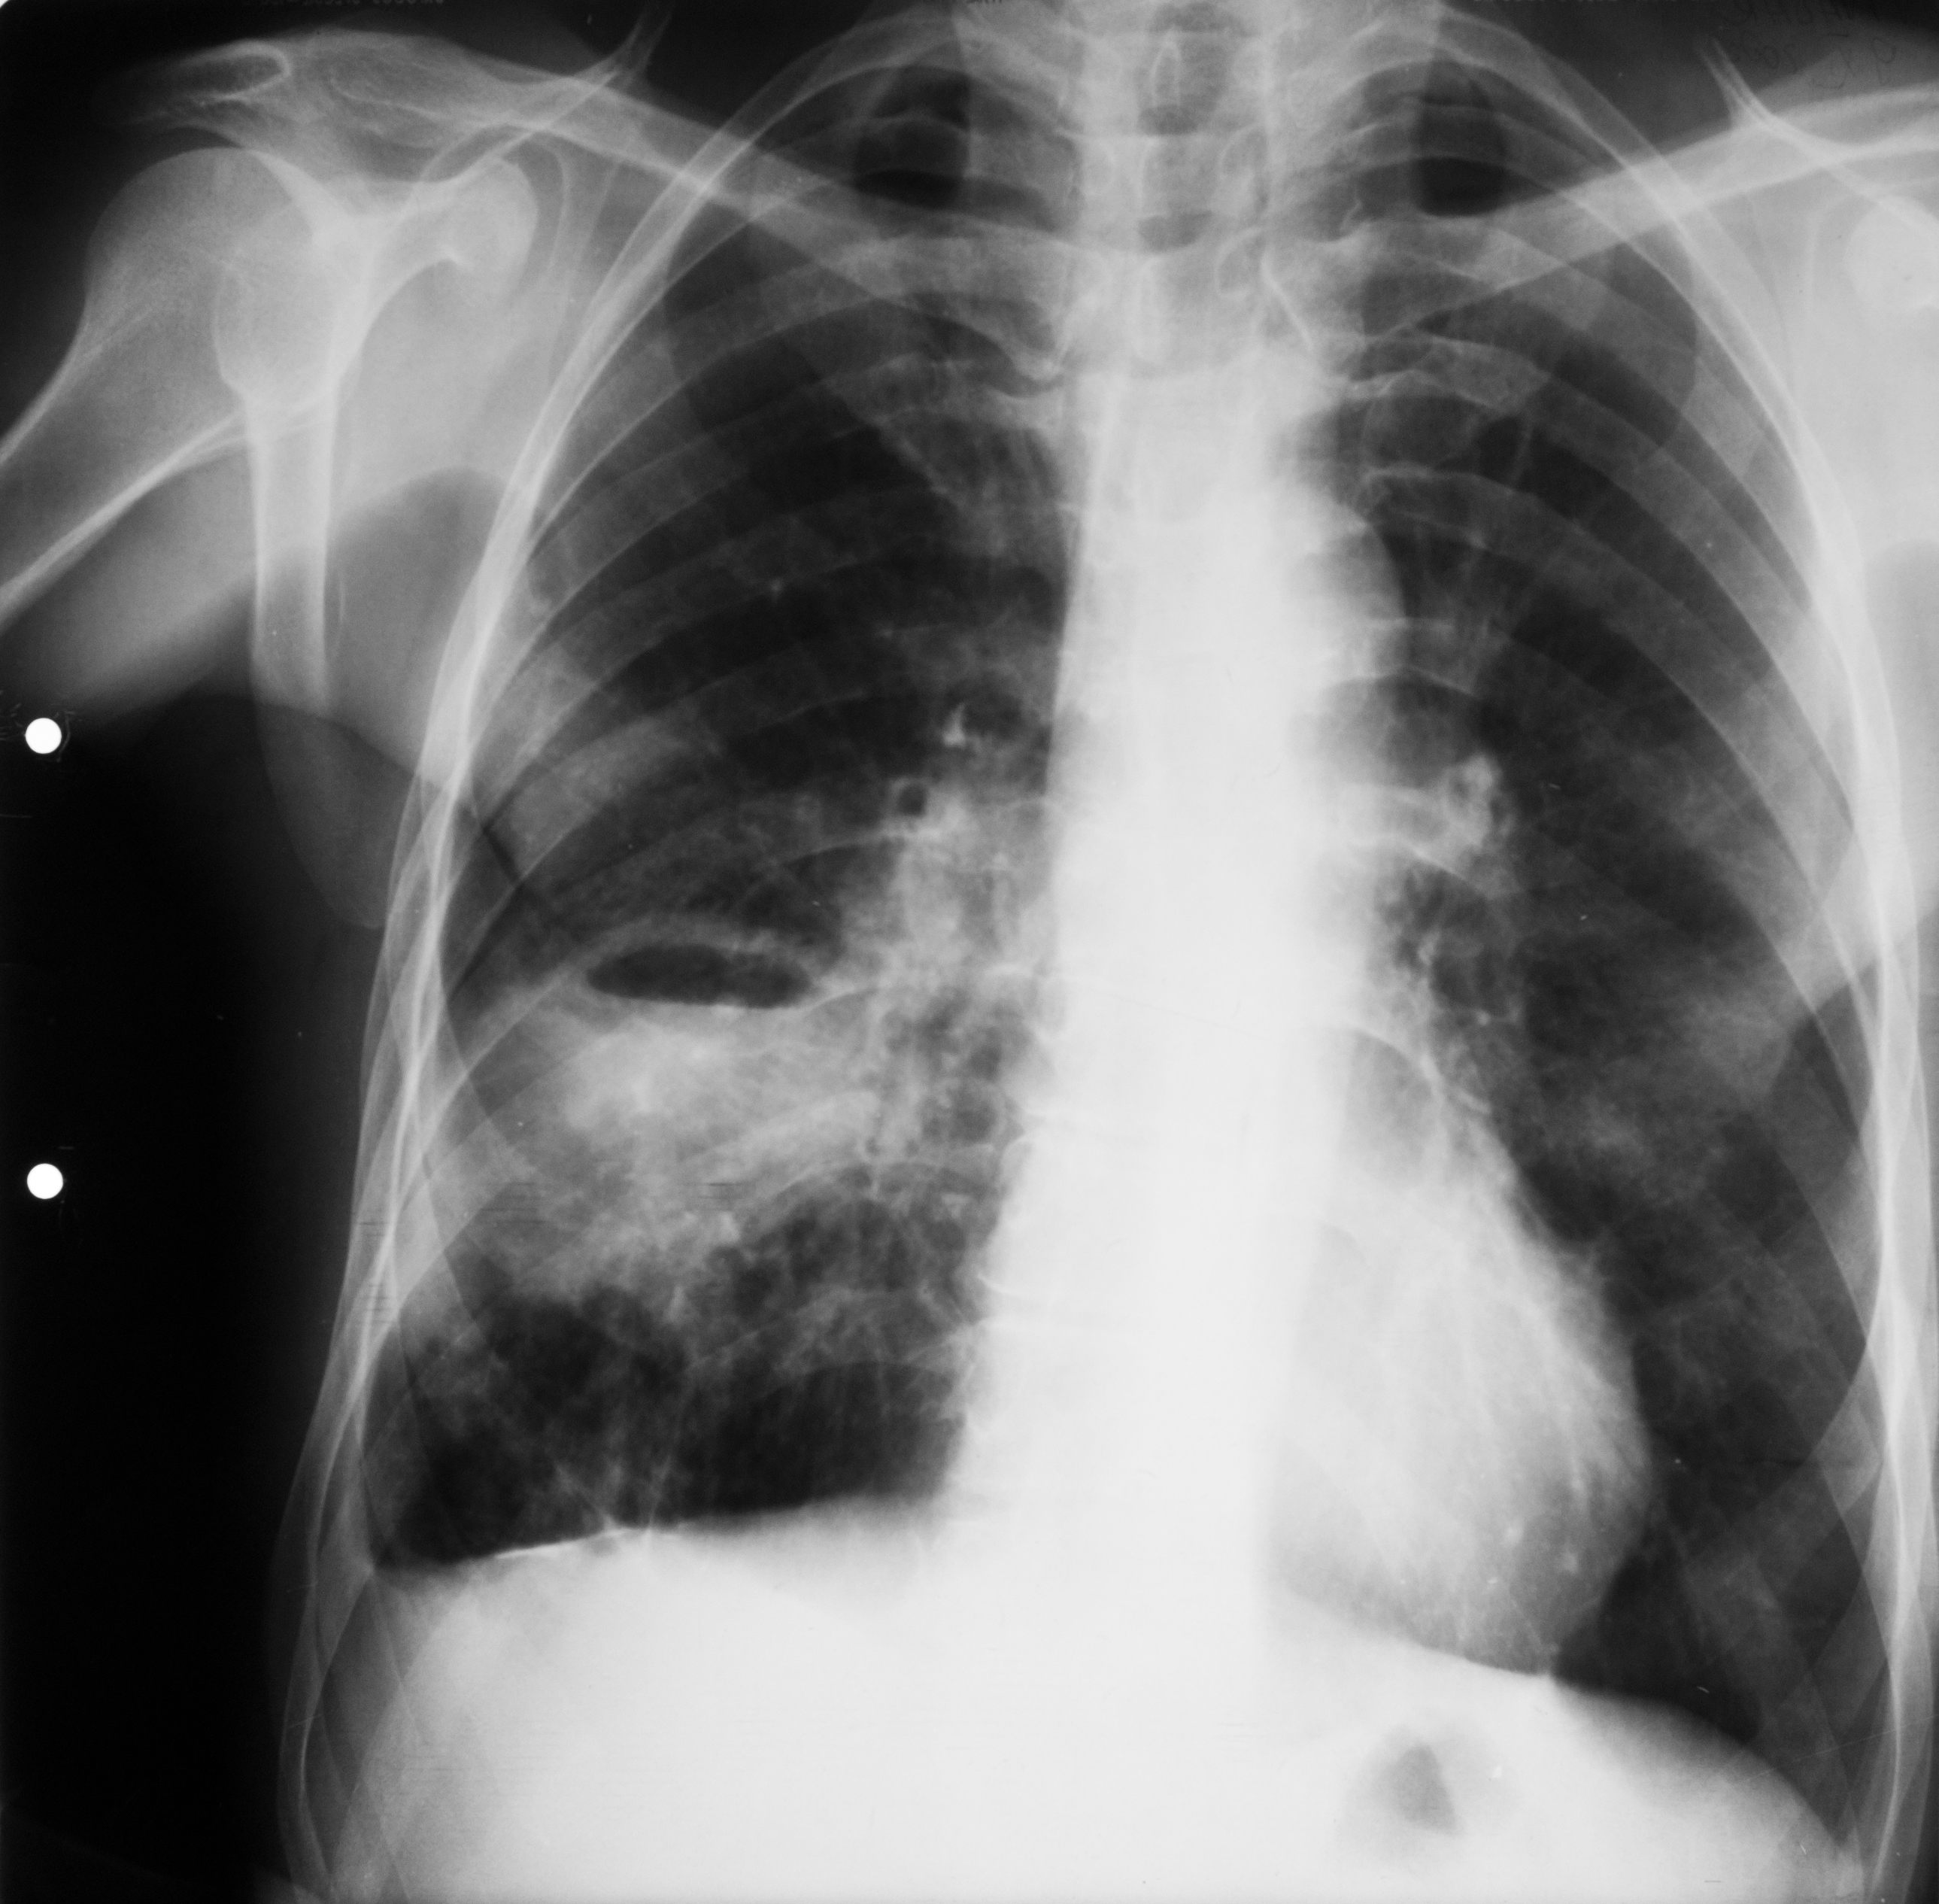

PNEUMONIE FRANCĂ LOBARĂ

Proces de condensare în jumătatea inferioară a câmpului pulmonar drept cu bronhogramă aerică ce vine în contact cu cordul

PNEUMONIE FRANCĂ LOBARĂ

Condensare cu bronhogramă aerică ce ocupă un lob întreg